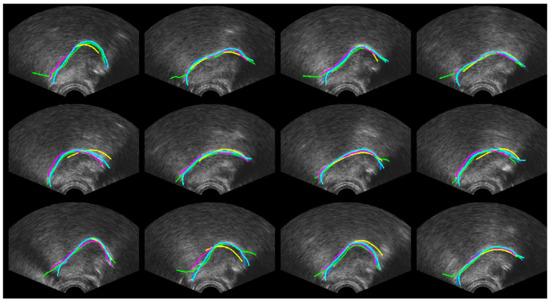

4.1. Ultrasound Contour Tracking